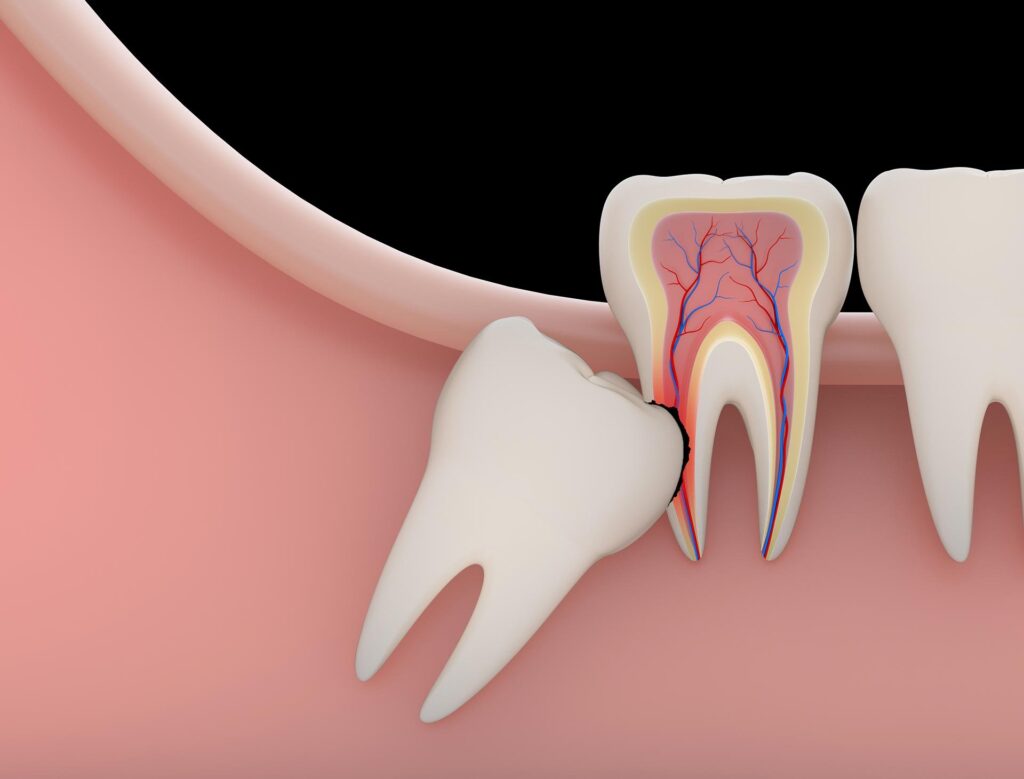

- Impaction: Wisdom teeth become affected when there is not enough room in the jaw for them to come in all the way. When teeth are impacted, they can hurt, get infections, and damage the teeth next to them.

- Damage to neighboring teeth: Wisdom teeth that are crowded or impacted can put pressure on nearby teeth, moving them out of place.